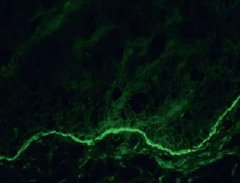

Lichenoid Drug Reaction 藥物 非直接性 IgG 螢光染色 → string of pearls (沿著複層鱗狀上皮的 basal cell layer 細胞膜) alt text